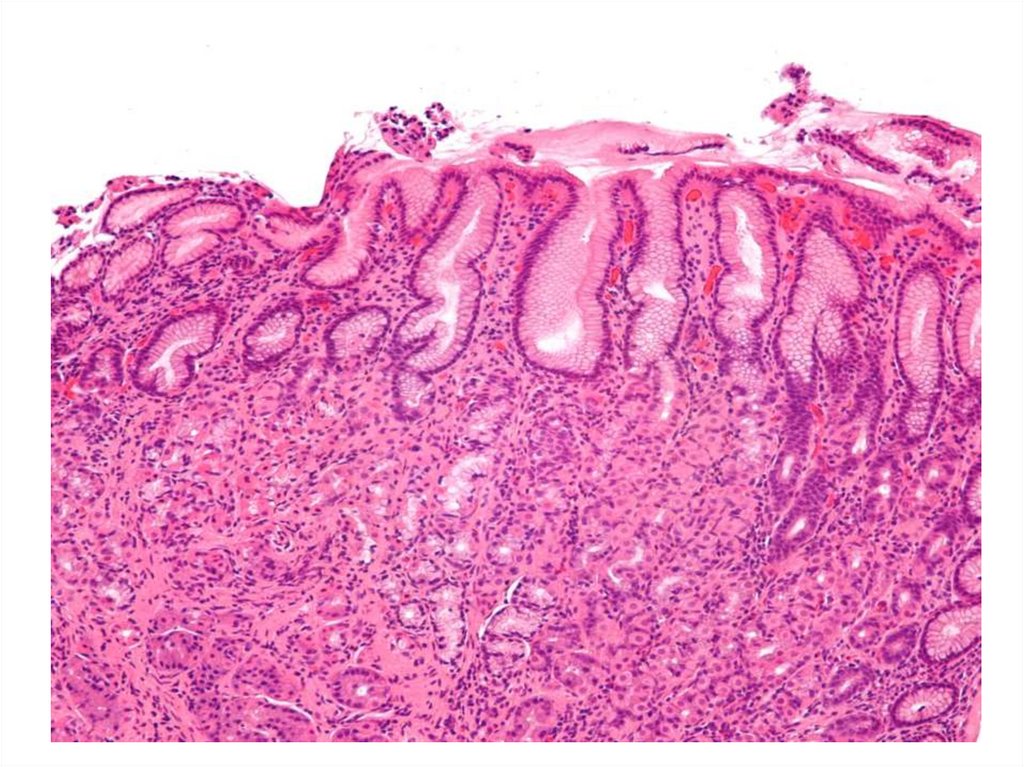

Гастрит

English     Русский Правила